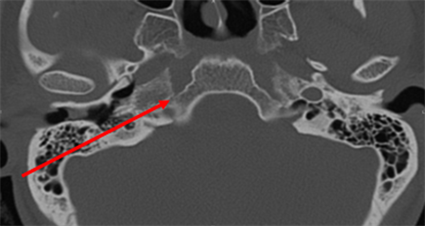

We report the case of a 24 years old female patient with vascular risk factors such as active smoking of 8 pack-years and a combined estrogen/progestin contraceptive. Her family history included an uncle with heterozygote factor V Leyden mutation. Presenting symptoms included a general feeling of being unwell without loss of consciousness, a mild dysarthria event and a fast-regressive left hemiparesis, with persistent weakness particularly in the left hand. Note that she had no headache. She was immediately admitted to the emergency department for thrombolysis. Brain scan and computed tomography (CT) Angiography of supra-aortic trunks completed with Magnetic Resonance Angiography (MRA) revealed ischemic stroke in the right sylvian territory affecting the parietal lobe, with no hemorrhagic conversion and no arterial occlusion [Figure 1]. Alternatively, magnetic resonance imaging (MRI) showed a vascular anatomic variant such as agenesis of the right internal carotid artery (ICA) with the right middle cerebral artery (MCA) fed through a dilated posterior communicating artery (PCOM) arising from the basilar artery [Figure 2; Figure 3]. CT scans at skull base level with bone settings showed absence of the right carotid canal, thus confirming agenesis, for which arteriography was requested [Figure 4]. Arteriography showed an operative circle of Willis, a MCA supplied by an enlarged right

Figure 4. CT scan of the skull base shows the absence of the right carotid canal. 24-year-old female patient (DAX hospital center).